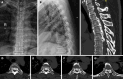

Case summary: A case of severe multi-segmental T-OPLL treated with thoracic anterior controllable antedisplacement fusion (TACAF) is reported, including the surgical procedures and analysis of the clinical data. The modified-Japanese Orthopaedic Association score in this patient was 4 before surgery, and it was raised to 9 after the operation. The symptoms of spinal canal compression were subsequently relieved. Three months after surgery, digital radiography showed good healing and recovery of limb sensory function.